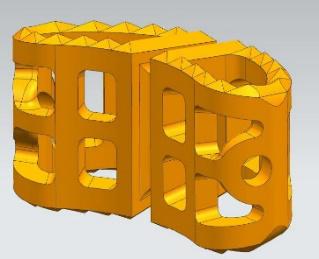

根據手術方案中的脊柱形態進行測量,定制個性化的假體和截骨導板。

定制個性化融合器 假體置于病例模型中